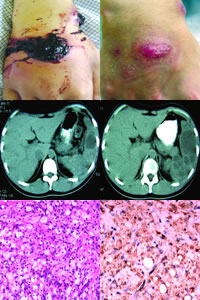

3.CT檢查診斷準確度高,敏感性和特異性均可達到90%。掃描檢查發現脾臟外形向外膨隆,脾內圓形或卵圓形低密度區,密度不均勻,邊緣不規則。膿腫內可見液平面或氣體,膿腫壁與脾實質相等。增強掃描時膿腫壁可增強,但膿腫內容物不增強。脾臟內可見散在的鈣化斑。

1.B超顯示脾臟增大,脾內單個或多個圓形、卵圓形或不規則的無回聲暗區,邊緣不平整,腔壁較厚。與脾臟囊腫相比,脾膿腫無回聲區邊緣回聲較強、模糊。無回聲區內有散在小點狀回聲影,可見液平,偶爾有氣體回聲。無回聲區後方回聲增強。約60%病灶在脾上極,可伴有左胸積液。